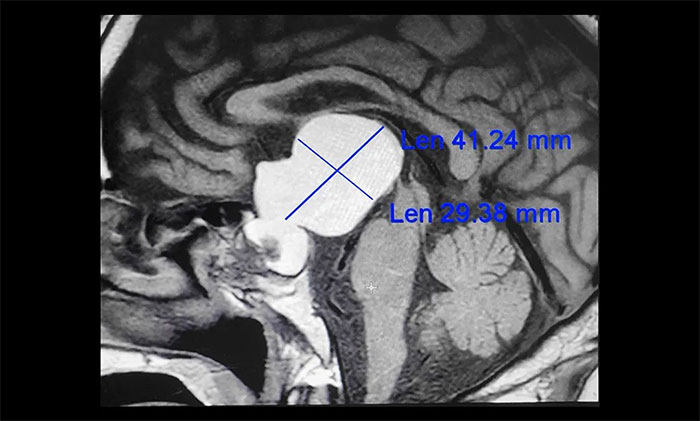

▲ 鞍區(qū)囊性占位病變

通過進(jìn)一步完善頭顱磁共振檢查,提示患者鞍區(qū)囊性占位病變,考慮為顱咽管瘤,瘤體最大直徑超過4cm。